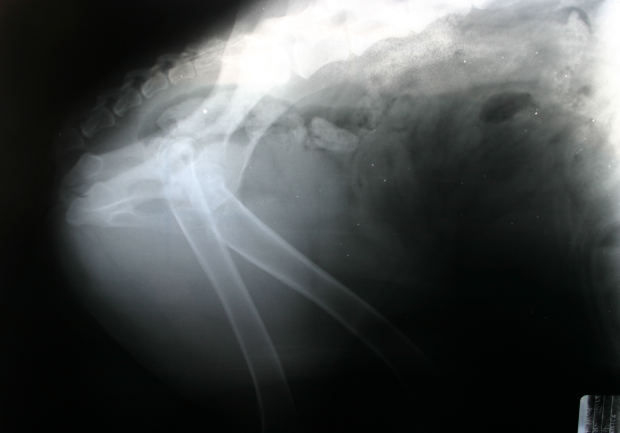

FDA zatwierdziła nowy lek tocilizumab (Actemra) dla wielostawowego młodzieńczego idiopatycznego zapalenia stawów (MIZS), poinformował producent preparatu – firma Genentech. Wcześniej tocilizumab został zatwierdzony do leczenia reumatoidalne zapalenie stawów również dla dorosłych. Jak podkreśla producent: dla dzieci w wieku od 2 lat wzwyż lek może być stosowny w monoterapii lub w połączeniu z metotreksatem.